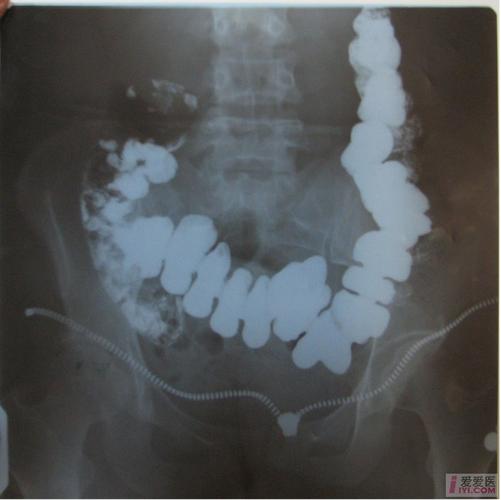

结肠梗阻结肠肠管扩张明显,升,降结肠区肠管内可见多个气液平面.